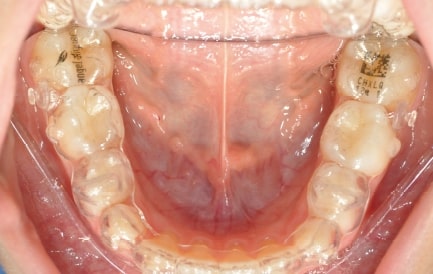

Initial Photos and datas

Clinical examination and diagnosis

DENTAL:

- Reduced Transversal Diameters

- Deviated Lower Midline 2 mm to the Right

- Upper Archform enlargement (dental expansion)

- Normalize Overjet/Overbite (Lower Posterior Extrusion)

- Alignment/Leveling Both Arches